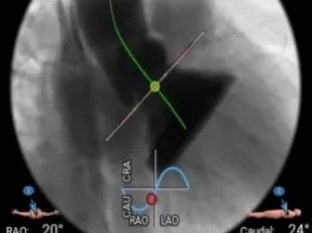

工作体位瓣膜释放

左右窦重合体位造影